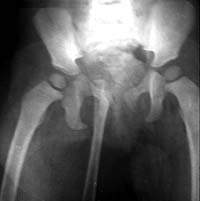

Диагностика и здоровье: Рентгенограммы таза